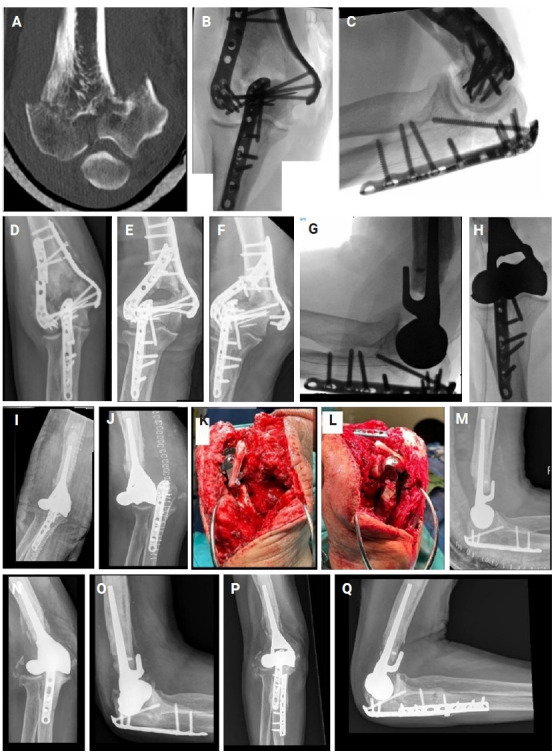

背景:评价肱骨远端半关节置换术(DHH)治疗8例肱骨远端骨折不可重建或切开复位内固定(ORIF)失败的患者的疗效。方法:回顾性资料包括人口统计学、术后结局和并发症,从一家一级创伤中心的电子记录中提取。手术由一名训练有素的上肢外科医生进行。DHH的适应症为肱骨远端不可重建骨折或ORIF失败。最终,正如当前文献所接受的那样,没有施加重量限制。在随访期间评估活动范围(ROM)、功能评分和疼痛水平。最小随访时间为12个月。结果:2014 - 2024年间,连续8例患者接受了DHH。手术时患者平均年龄为68.1岁,平均随访46.6个月。患者表现出满意的关节活动度,前旋接近完全,平均屈伸分别为125°和25°。功能评分,包括手臂、肩膀和手的快速残疾评分(35.2)和Mayo肘部表现评分(78.1),均良好。平均数值疼痛评定量表为3.9。并发症包括2例因肘关节不稳定和术后感染而进行全肘关节置换术(分期转换),1例因肘关节术后不稳定而进行韧带重建,2例尺假体周围骨折,1例尺神经病变。结论:对于无法重建的肱骨远端骨折和ORIF失败的DHH,允许无限制的术后抬起,并产生令人满意的功能结果,但确实有相对较高的并发症发生率。证据等级:四级。

Background: To evaluate the outcomes of distal humerus hemiarthroplasty (DHH) in a series of eight consecutive patients with unreconstructible distal humeral fractures or failed open reduction and internal fixation (ORIF).

Methods: Retrospective data including demographics, postoperative outcomes, and complications were extracted from electronic records at a level 1 trauma center. Surgeries were performed by a single fellowship-trained upper extremity surgeon. The indications for DHH were unreconstructible distal humerus fracture or failed ORIF. Eventually, as accepted by current literature, no weight restrictions were applied. Range of motion (ROM), functional scores, and pain levels were evaluated during follow-up appointments. Minimum follow-up time was 12 months.

Results: Between 2014 and 2024, eight consecutive patients underwent DHH. The mean patient age at the time of surgery was 68.1 years, with an average follow-up of 46.6 months. Patients exhibited satisfactory ROM, with near-complete pronosupination and mean flexion and extension of 125° and 25°, respectively. Functional scores, including Quick Disabilities of the Arm, Shoulder and Hand score (35.2) and Mayo Elbow Performance Score (78.1), were good. Mean Numeric Pain Rating Scale was 3.9. Complications included two conversions to total elbow arthroplasty due to elbow instability and postoperative infection (staged conversion), one ligament reconstruction for postoperative elbow instability, two cases of ulnar periprosthetic fracture, and one case of ulnar nerve neuropathy.

Conclusions: DHH for unreconstructible distal humerus fractures and failed ORIF allows for unrestricted postoperative lifting and yields satisfactory functional outcomes but does have a relatively high complication rate. Level of evidence: IV.